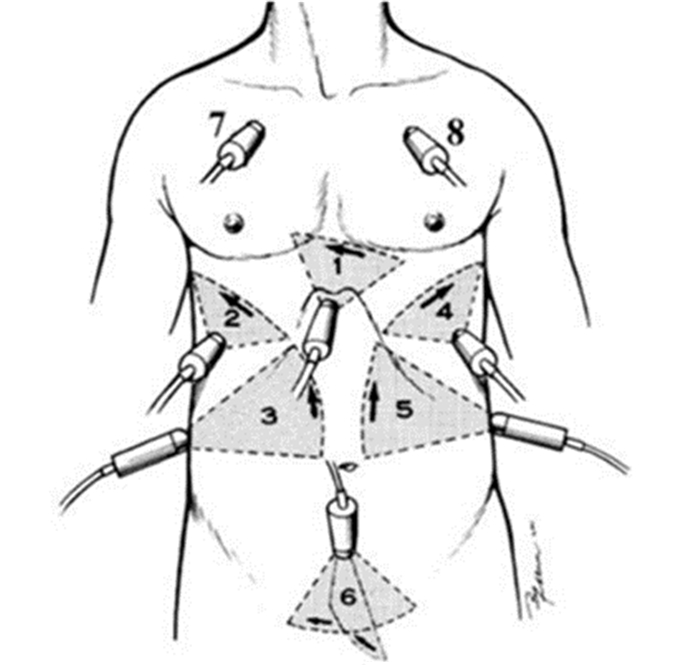

3 超声的临床应用 3.1 床旁超声在创伤中的临床应用 3.1.1 概述外伤患者病情危重且复杂,部分患者外伤后昏迷或被动体位,不能有效配合检查,而各种危重外伤患者的救治都有一个“黄金时段”,因此需要找到一种快速、科学的检查方法,从而最大限度地降低外伤患者的病死率。20世纪80年代末,国外提出针对创伤的超声快速评估法,即FAST(focused assessment with sonography for trauma)[4, 5]技术,目前已成为急重症医师快速床旁评估急性胸腹部闭合性损伤患者病情最重要的工具。传统FAST检查主要利用超声快速判断腹腔有无游离积液,扩展的FAST检查(EFAST)内容扩展到包括胸腔、心包检测[6, 7]。FAST通过对胸腔、心包、腹腔以及骨盆等部位检查,判断是否存在积液(图 21)。FAST可识别由于脏器损伤而溢出的游离液体及气体,而游离液体/气体往往是器官损伤的标志。

| 图 21 EFAST探头检查部位 |

3.1.3 创伤的超声诊断的步骤及流程(1)创伤的超声诊断步骤:创伤患者床旁超声检查至少5个部位:①右上腹,也叫肝周切面、莫里森窝切面或右上1/4切面。如出现无回声区提示腹腔内出血(图 22-23)。②左上腹脾肾间隙,如出现无回声区亦提示腹腔内出血(图 24-25);③耻骨上/盆腔切面,如显示膀胱后或子宫后无回声区,提示盆腔出血可能(图 26-27);④剑突下切面,常用于探查心包有无无回声区(图 28),具体心包积液征象见2.1.2 常见异常超声心动声像图。⑤肺部超声,主要用于探查有无血气胸、肋骨骨折,具体征象见2.2肺超声。